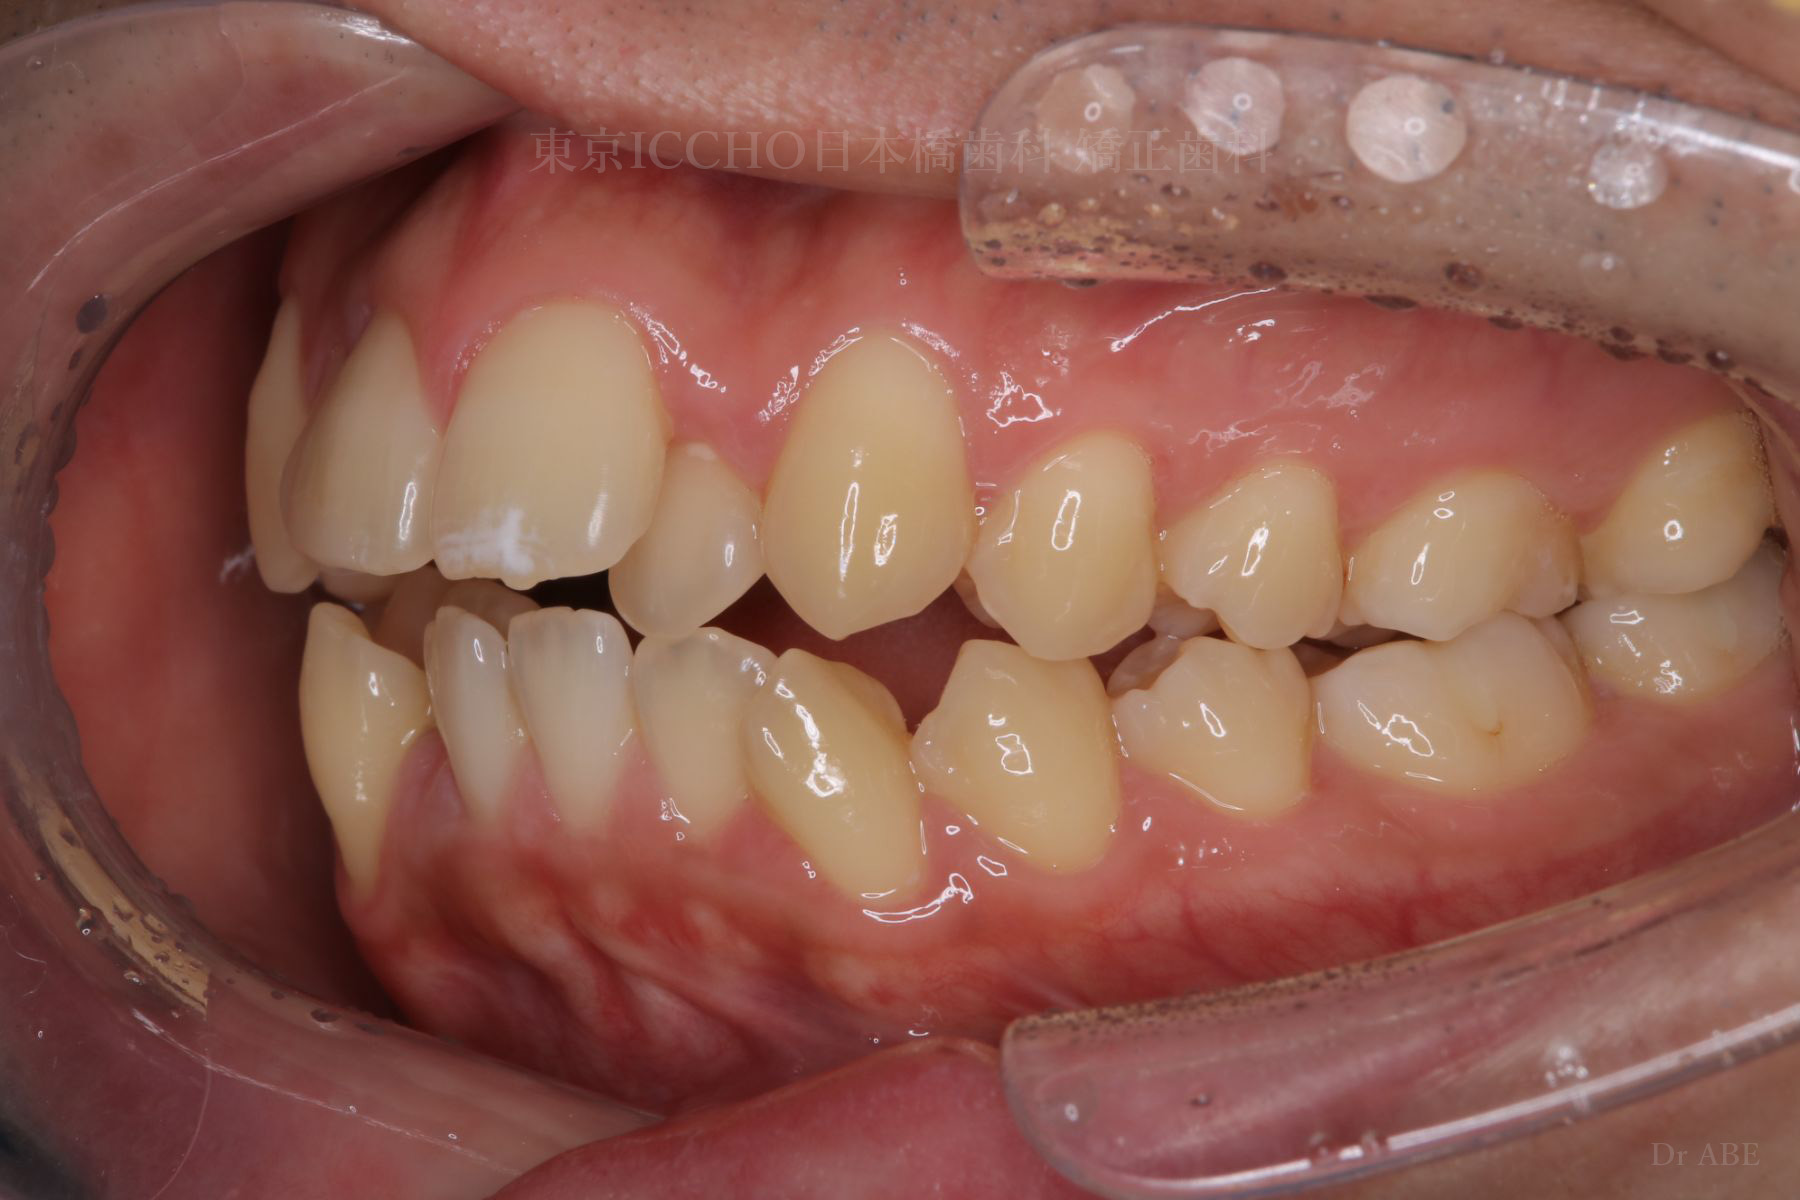

治療後

治療内容 かみ合わせの不正と顎が小さいため、上下左右第一小臼歯4本の抜歯を行い前歯を後ろへ下げた。

また、前歯が噛まない状態のため、かみ合わせを少し下げて噛むように誘導し、全体的にかみ合わせとして機能的な矯正治療を行った。